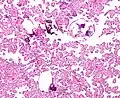

The tumor is neuroectodermal in origin and similar in structure to a normal choroid plexus. They may be created by epithelial cells of the choroid plexus. Papillary fronds lined by bland columnar epithelium are visible under the microscope. Normal absences include mitotic activity, nuclear pleomorphism, and necrosis.[10] Tumors have positive immunohistochemistry for cytokeratin, vimentin, podoplanin, and S-100.[11] Up to 20% of choroid plexus papilloma patients may test positive for glial fibrillary acidic protein (GFAP).[12] Studies have found that fourth ventricle cancers express more S100 than lateral ventricle tumors, and older patients (over 20 years) express more GFAP and transthyretin than younger patients.[13] Some individuals with choroid plexus papilloma have germline TP53 gene mutations, according to genetic analyses.[14] These cancers rarely exhibit nuclear p53 protein positivity. Aicardi syndrome, hypomelanosis of Ito, and 9p duplication are syndromic correlations of choroid plexus papilloma.

Micrograph of a choroid plexus papilloma. H&E stain.